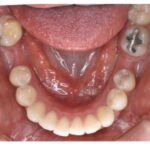

歯科矯正治療の中でも舌側矯正(裏側矯正)は、最も難易度が高いと言われています。矯正医でも難しいとされる舌側矯正においての症例数(実績)が多いのが恵比寿エスト矯正歯科の特徴です。